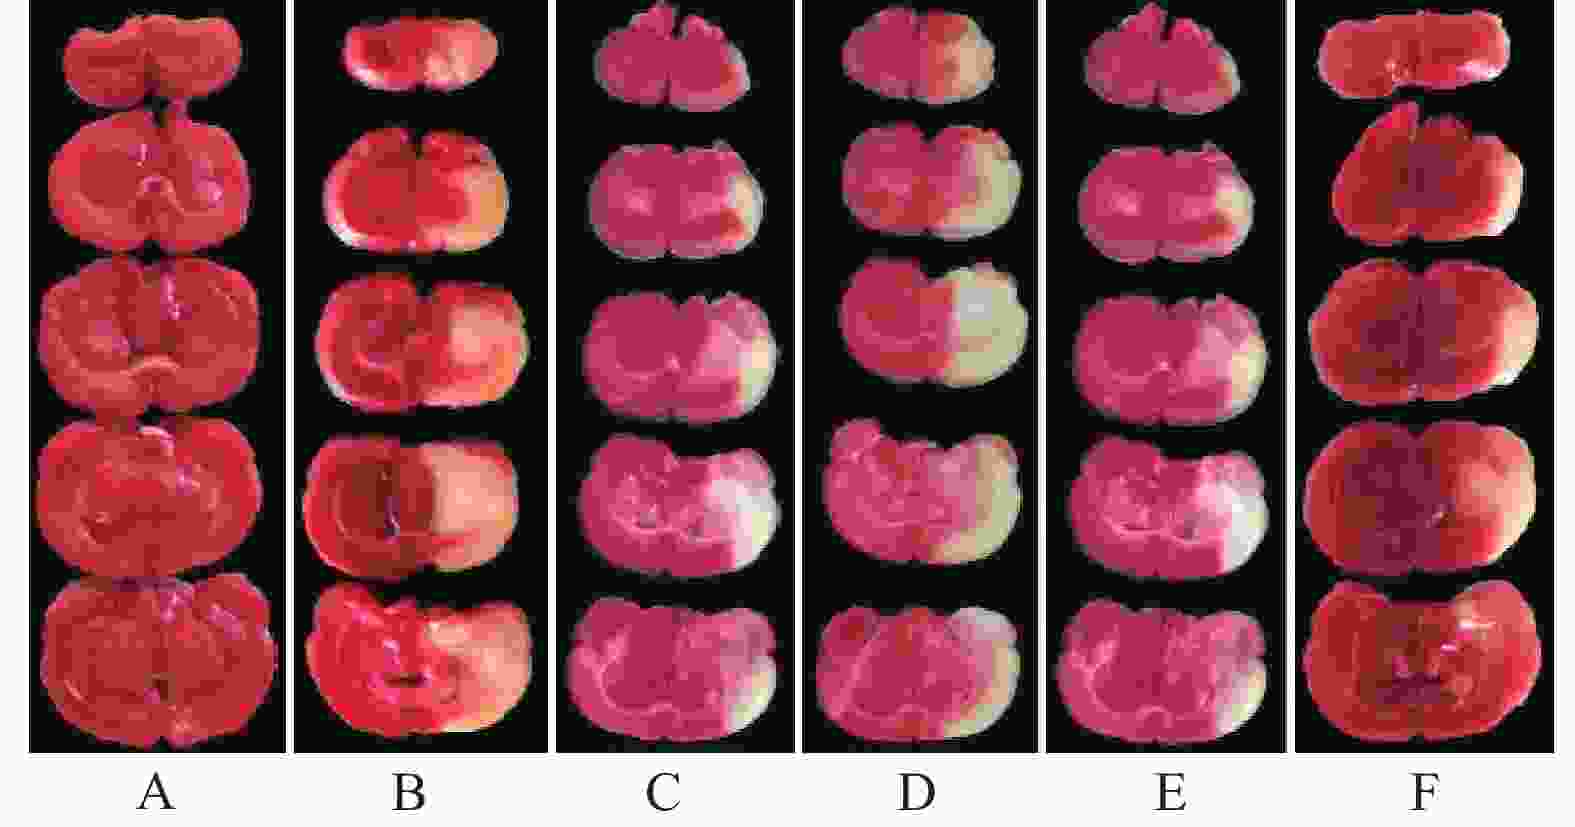

再灌注24 h后,分别随机取各组6只大鼠,参照文献报道的方法[13]进行神经功能缺失评分,无症状为0分、前肢不能伸展为1分、行走时转圈为2分、行走时跌倒为3分、不能行走或意识丧失为4分。ip戊巴比妥钠(40 mg/kg)进行麻醉后,颈椎脱臼处死,取大脑组织、−20 ℃冻存15 min后均匀厚度切为5片,2% TTC溶液恒温37 ℃避光染色30 min,每5 min翻转一次,正常组织呈红色、梗死组织呈苍白色,通过图像分析软件计算脑梗死率。

与假手术组比较,模型组大鼠神经功能缺失评分和脑梗死率显著升高(P<0.05)。与模型组比较,雷公藤甲素中、高剂量组和丁苯酞组神经功能缺失评分和脑梗死率显著降低(P<0.05)。与丁苯酞组比较,雷公藤甲素高剂量组神经功能缺失评分和脑梗死率显著降低(P<0.05)。见图1、表1。

假手术组大鼠皮层神经元呈圆形或椭圆形,形态饱满,着色均匀,胞核居中。模型组大鼠缺血半暗带皮层神经元呈现形态不规则,胞体萎缩呈空泡样变,着色较深,核膜边界不清,炎性细胞浸润等病理学改变。与模型组比较,雷公藤甲素各剂量组和丁苯酞组缺血半暗带皮层神经元明显改善,其中雷公藤甲素高剂量组效果优于雷公藤甲素低、中剂量组和丁苯酞组,见图2。

线栓法是CIRI动物模型制备的经典方法,具有操作简便、重复率高、与人类临床病理接近等优点。本实验结果显示,CIRI模型大鼠呈现明显的神经功能障碍,BBB通透性异常升高,缺血半暗带大脑皮层神经元呈现形态不规则、胞体萎缩呈空泡样变、着色较深、核膜边界不清、炎性细胞浸润等病理学改变,与杨欢欢等[15]研究结果一致。本研究发现,经雷公藤甲素中、高剂量或丁苯酞预处理能够明显改善CIRI大鼠神经功能,降低脑梗死率和BBB通透性,改善缺血半暗带大脑皮层神经元病变并降低其凋亡率,并且雷公藤甲素高剂量组效果优于丁苯酞组;而雷公藤甲素低剂量组上述作用并不显著。说明雷公藤甲素具有抑制大鼠CIRI的作用,该作用具有一定的剂量依赖性。